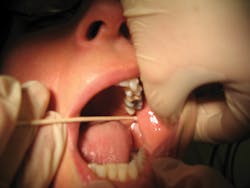

The V-A block is also useful when soft-tissue structures, such as the tongue or buccal fat pad, persistently obstruct the view of the necessary intraoral landmarks used in the IA block (see Figure 3).2,3 In addition, this block can be used for the fearful patient who does not want to open for anesthesia or may not be able to hold his or her mouth open for the length of injection.2,3 Pain levels using the visual analog scale (VAS, which is a tool used to help a person rate the intensity of certain sensations and feelings such as pain) are similar to the other mandibular quadrant blocks, the IA and G-G blocks. This moderate level can be mediated by using pain control methods such as anesthetic buffering and nitrous oxide inhalation.2,3,7,9 In fact, one clinical trial found that the V-A block was "subjectively most acceptable to the patient."10

Figure 3: An obstructing tongue and/or buccal fat pad on one patient was noted during palpation by the cotton swab before the administration of an inferior alveolar block during two separate appointments. These persistently individualized anatomic features prevent the clinician from viewing the necessary intraoral landmarks for that block. This could prevent the needle from accessing the target area of the pterygomandibular space. Consideration of using the Vazirani-Akinosi mandibular block was then pursued for future dental hygiene care on the patient's mandibular arch. These obstructions can be commonly noted on many patients. (courtesy of Margaret J. Fehrenbach, RDH, MS)